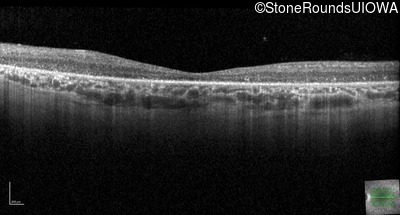

Optical Coherence Tomography - Right - 20/400 sc

Exemplar / OCT Stack

OCT Stack

Optical Coherence Tomography - Left - 20/300 sc